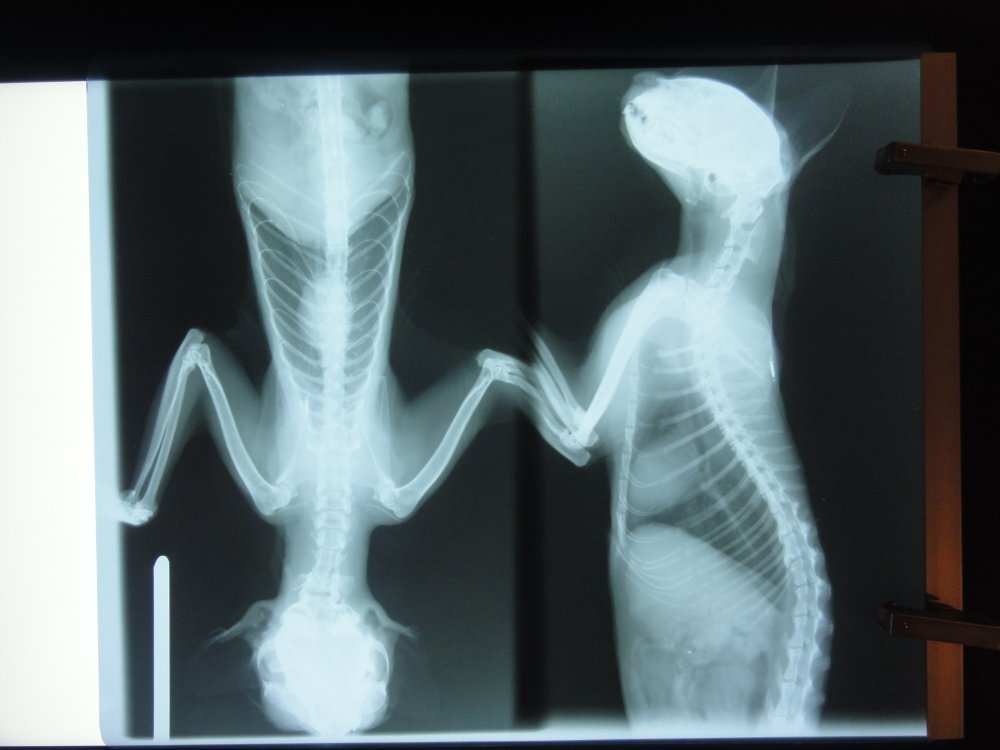

主題: 廈安里奶油白TNR母貓治療 申請者姓名: Akimasa Tu 花色: 申請日期: 2012-04-28 20:32:12 申請者部落格: https://www.facebook.com/media/set/?set=a.325191994205701.74991.100001447087354&type=3 申請者臉書網址: https://www.facebook.com/akimasa.tu?ref=tn_tnmn 所在縣市/合作醫院: 台北市/長沁動物醫院 治療費用: 35280元 需求人數: 40人 已結案 (2012-11-25 22:00:51) 報名人員: 嘎嘎(已付款)、婷寶貝(已付款)、Ping Hussard(已付款)、Maggie Kuai(已付款)、Maggie Kuai(已付款)、反核星啵(已付款)、Jessica C. Chang、吉蘿琳(已付款)、林飄飄(已付款)、曾沛華(已付款)、鄭古萬(已付款)、Vicky Huang(已付款)、Melody Wu(已付款)、Lily Jian(已付款)、sherry(已付款)、Joy、Joy(已付款)、笨姐姐(已付款)、Akimasa Tu(已付款)、Akimasa Tu(已付款)、Akimasa Tu(已付款)、Akimasa Tu(已付款)、Akimasa Tu(已付款)、小節(已付款)、Ku-ai Gina Chen(已付款)、Olive Chen(已付款)、阿吉(已付款)、煌邵(已付款)、Jennifer Hu(已付款)、A.k. Liu(已付款)、HuaMing Sung(已付款)、吳俊儀(已付款)、饅頭(已付款)、OLivia Lee(已付款)、大雨(已付款)、大雨(已付款)、SHIN HUI(已付款)、Chin-Fei Huang(已付款)、Ingriddec Wang(已付款)、Chang YaChi(已付款)、柯小芳(已付款)、Estella Chen(已付款)、 候補人員: 小舟、小舟、小舟、小舟、小舟、 動物病情說明: 此貓是3月3日,由萬華志工簡小姐,於廈安里TNR的奶油色母貓,放回後一段時間,發現情況非常的糟,簡小姐又帶去治療,有非常嚴重的感冒症狀及口腔潰爛,牙齒嚴重結石等問題,並照X光,確認肺部正常無病變,住院期間長期接受霧化治療,並洗牙、治療口腔問題,病狀也明顯改善。

但住院期間血檢,白血球一直異常,高達9萬以上,雖其他狀況都已改善,但白血球一直降不下來,後來做細菌培養才發現,這貓體內有某種超級細菌,導致白血球異常,使用一般抗生素治療無效,只能用"萬古黴素",並與其他輸液,由皮下注射方式治療。

此貓被檢出有超級細菌,原本一度想將他安樂,因為放回後可能造成集體感染,中途又怕傳染其他貓咪,所以很難做決定,後來由長沁張醫師,致電給Mindy,討論治療方式、費用及時間,還是決定投葯救這隻貓,經過約一星期注射"萬古黴素"後,白血球降至正常值,投葯約10天後,此貓出院,由簡小姐帶回,已不考慮野放,先中途,待貓恢復元氣後,再安排送養事宜。動物近況說明: 20120507補充說明: